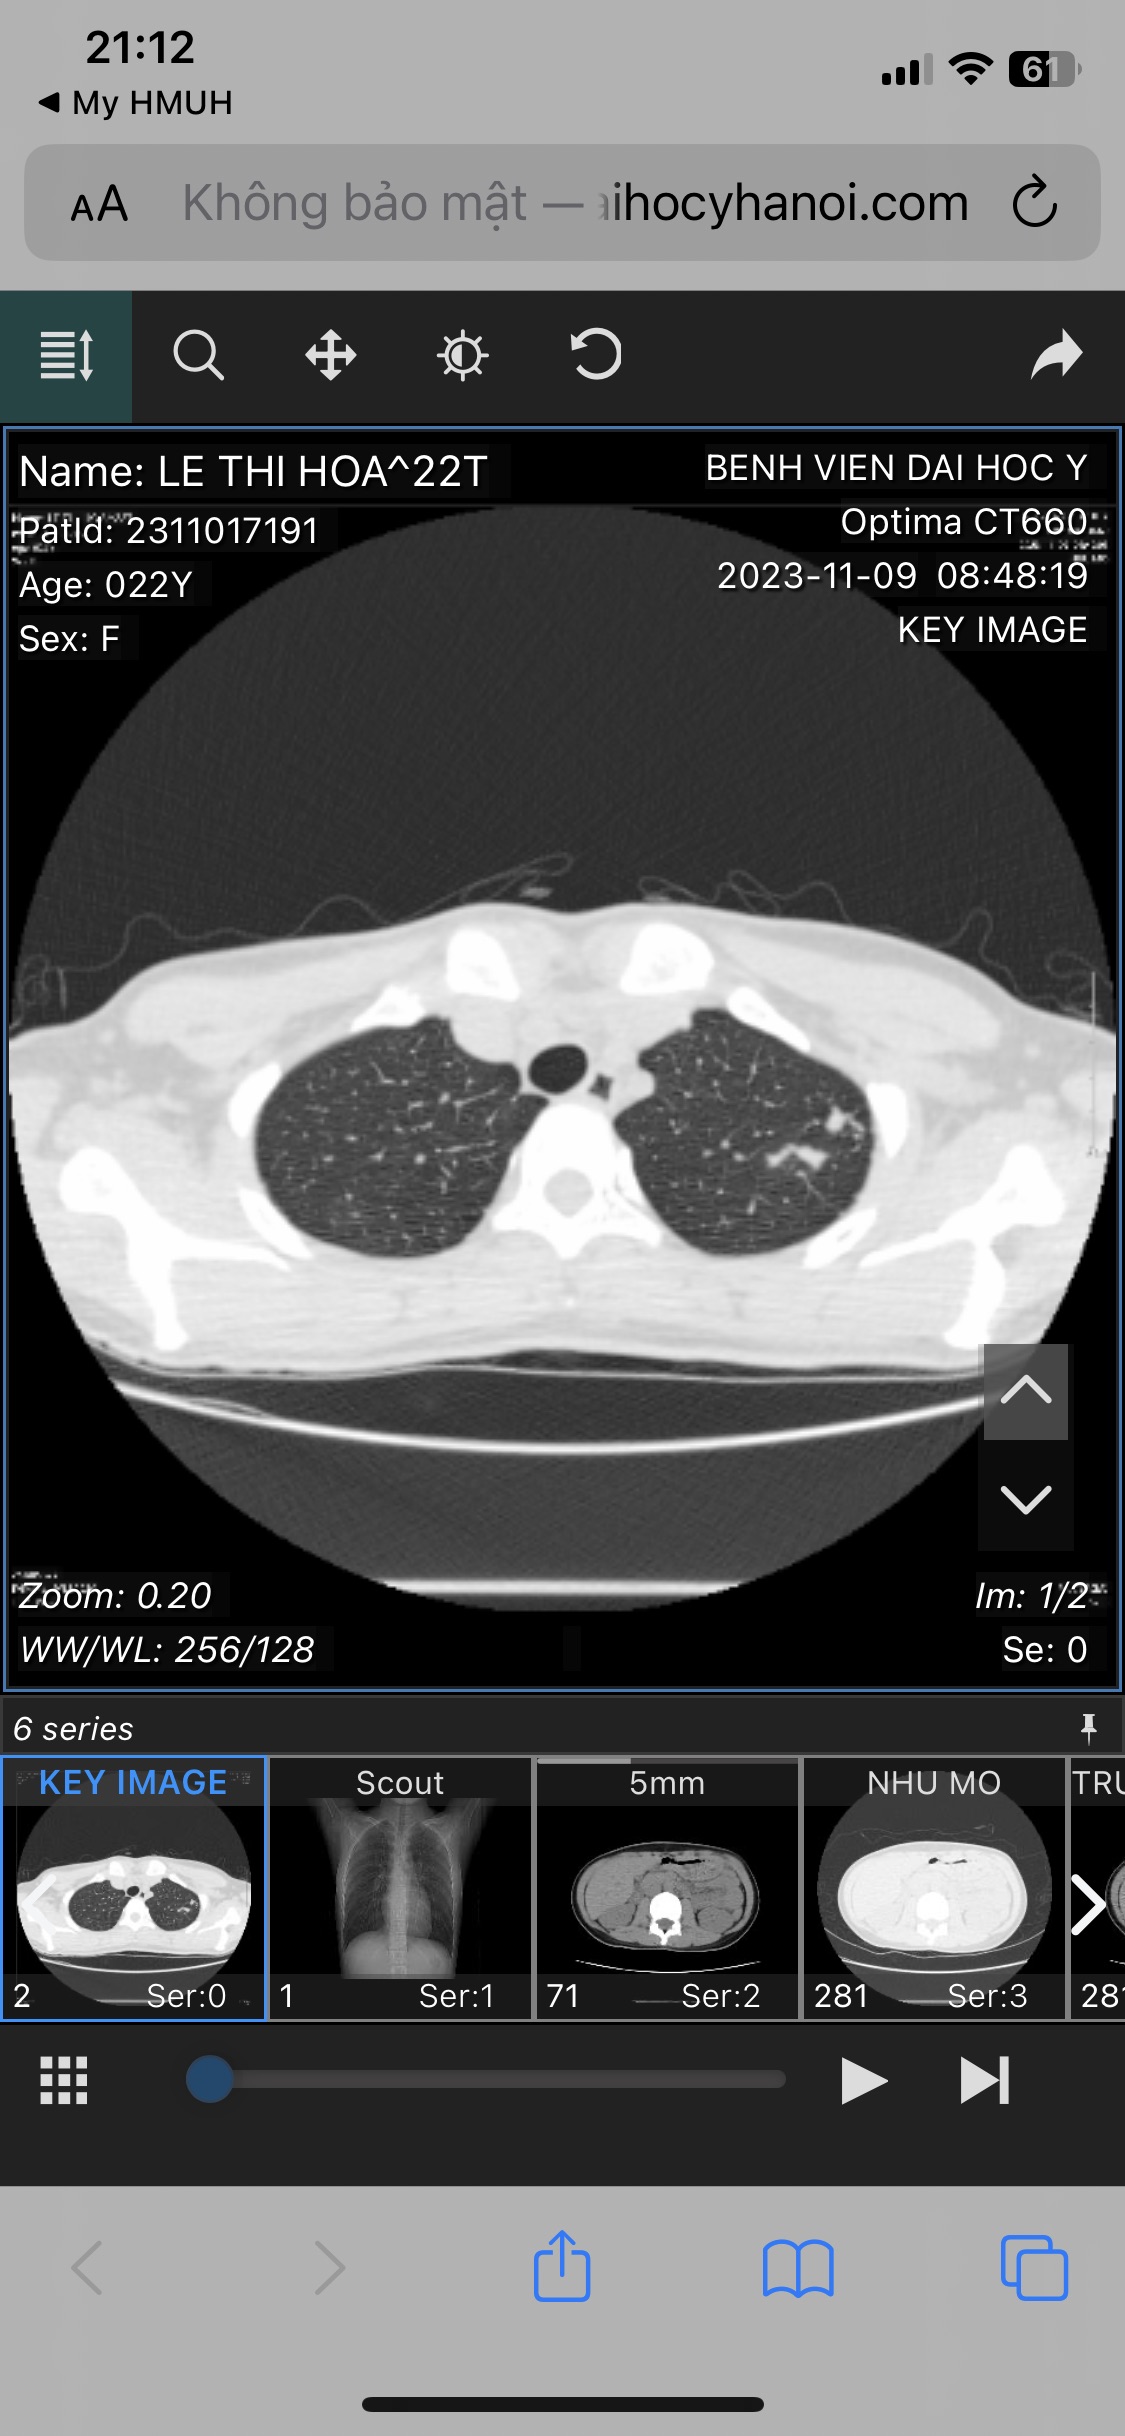

Bác sĩ cho e hỏi . Em được chuẩn đoán lao phổi không có triệu chứng gì . Đã có nội soi phế quản và kết quả đều âm tính . Gần đây thường xuyên bị tức ngực nhiều . Có phải bệnh đã chuyển nặng . Em mong bác sĩ giải đáp ạ

E không có dịch đờm . Chỉ làm nội soi phế quản và kết quả âm tính cả nấm phổi và cả lao . Hiện tại không dùng thuốc gì ạ

Vậy bác sĩ chẩn đoán cuối cùng là gì em. Chưa có bằng chứng về Lao